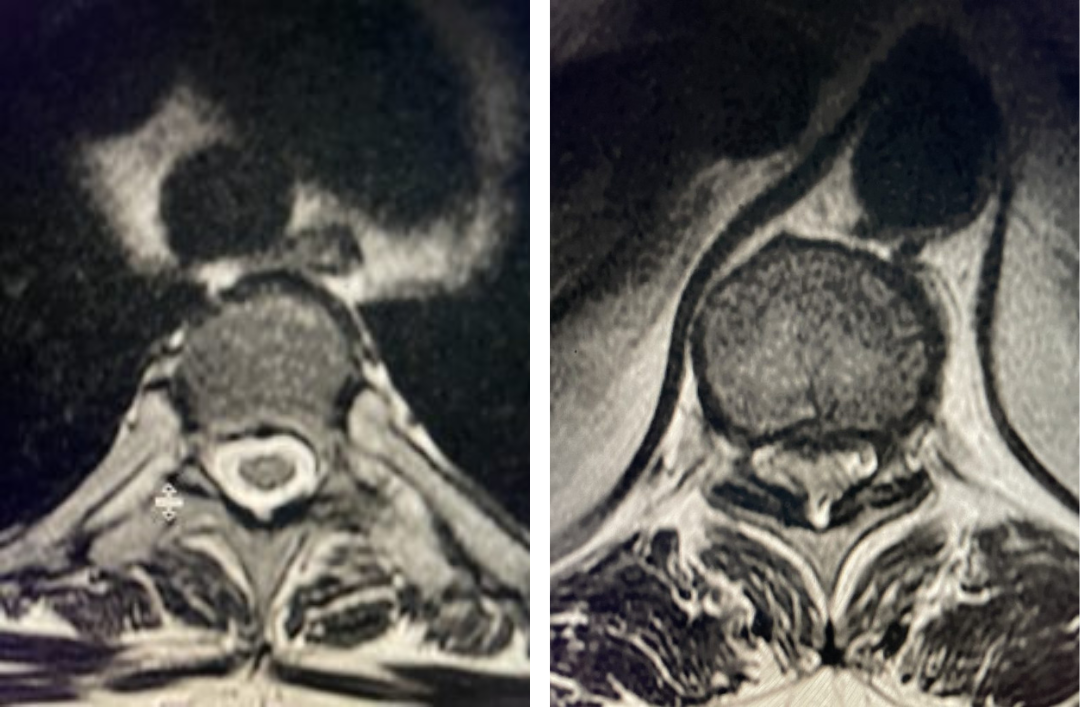

Fig 4: Axial and Sagittal T2-weighted lumbar MRI demonstrating a left lateral foraminal disc herniation (red arrow) causing compression of the exiting L1 nerve root against the undersurface of the pedicle of L1.

As an example of this type of pain syndrome, an interesting 58-year-old female presented with “soreness” and numbness of her left groin area for 6 months. She had no leg or back pain, weakness, or bowel or bladder dysfunction. She sought gynecological care, for which she had a pelvic examination. The examination elicited pain on left-sided palpation. She had negative imaging of her pelvis. Her family physician ordered a lumbar MRI, which revealed a left foraminal disc herniation compressing the left L1 root superiorly against the L1 pedicle (Fig 4). Clearly the numbness was in an L1 dermatomal distribution and correlated with the patient’s MRI. We started the patient on Medrol and Neurontin. We referred her to pain management for a left L1-2 transforaminal epidural and will follow her up in 6 weeks. If her problem does not resolve, we will offer surgical removal. It is important to realize that many patients with spinal pathology can present pain syndromes that mimic other conditions. For example, a patient may have an upper thoracic compression fracture with pain referred to the anterior chest wall, which can cause the patient to feel like they are having a heart attack. It is only during a cardiac workup that they discover the underlying problem with a chest x-ray.